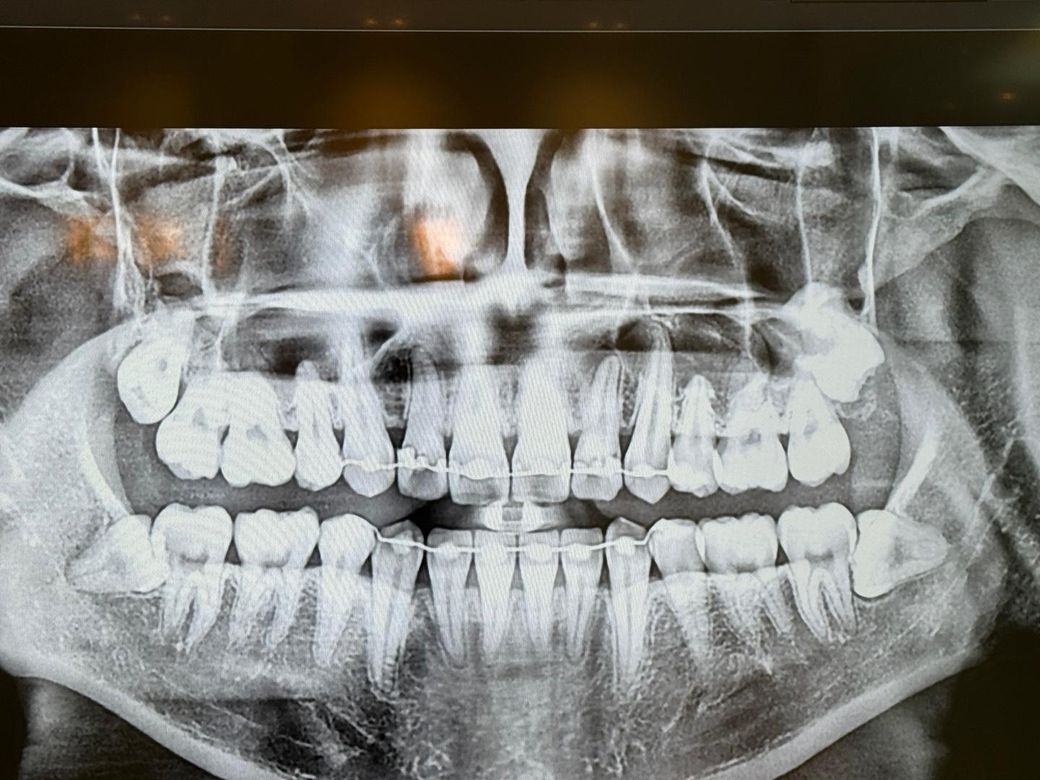

치과의사분들 파노라마 사진 봐주세요

25 06월입니다 혹시 문제점있나 봐주실수있으실까요

치료해야되는부분이나 미리감사합니다

아프거나 시린곳은 없습니다

• 2번 째 사진

파노라마 상으로는 어금니 치아 사이에 충치가 잇는것처럼 보이는곳도 잇으니 치과에가셔서 작은사진을 몇장 찍어보시는게 좋을것같습니다.

사진으로는 크게 문제가 있는 것이 보이진 않습니다. 하지만 육안상으로 작은 충치들이 있을 수 있기 때문에 자세한 확인을 위해서 치과에서 진료를 받아보는 것을 권유드립니다.

잇몸뼈 높이 변화 크게 없고요 특별히 치료가 시급한 큰 충치도 보이진 않습니다 다만 오른쪽 아래 사랑니는 발치 고려해봐야 할 것 같습니다